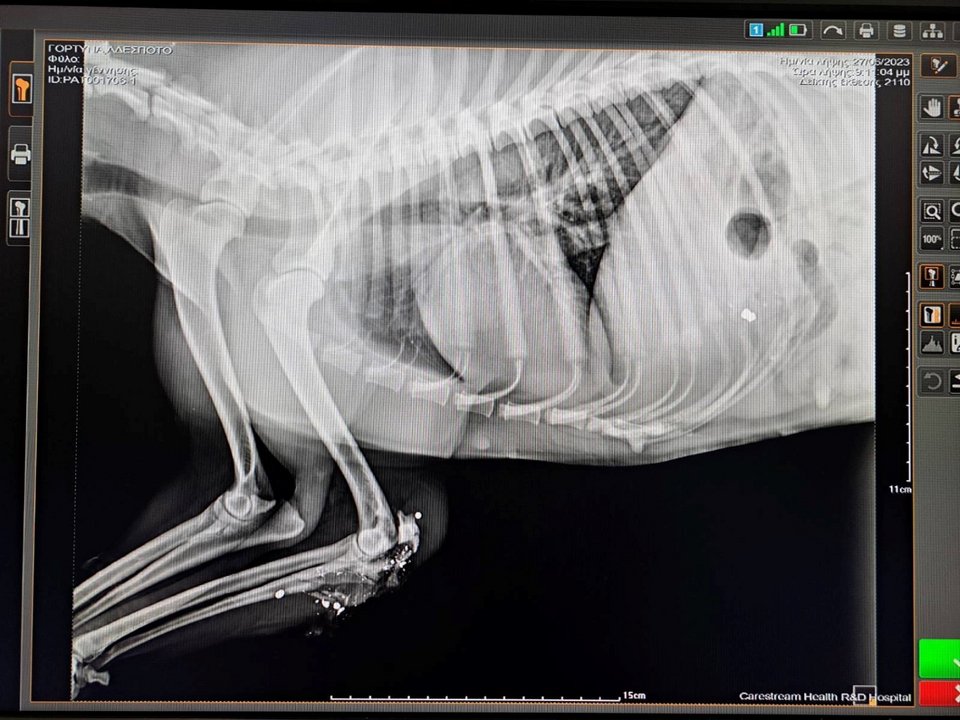

Συγκεκριμένα και σύμφωνα με το cretapost.gr, μέσα σε λίγες ημέρες έχει καταγραφεί ένας βάρβαρος ευνουχισμός σκύλου με μεταλλικό tire up στην περιοχή της Αμμουδάρας του Ηρακλείου, ένας βάναυσος ακρωτηριασμός βελγικού λυκόσκυλου στο Ρέθυμνο, και ο πυροβολισμός ενός αδέσποτου στην περιοχή της Αγίας Βαρβάρας, το οποίο χρειάστηκε να ακρωτηριαστεί για να σωθεί η ζωή του.

Χαρακτηριστική είναι η ανακοίνωση που εξέδωσε η φιλοζωική ομάδα «Σείριος» η οποία αναφέρει σχετικά: «Τα δυο απαράδεκτα περιστατικά που καταγράφονται τα τελευταία 24ωρα, με τον βάναυσο ακρωτηριασμό του βελγικού λυκόσκυλου στο Ρέθυμνο και το βάρβαρο ευνουχισμό με δεματικό, σκυλιού που βρέθηκε στην Αμμουδάρα Ηρακλείου, είναι απόλυτα καταδικαστέα. Όσο και ο πυροβολισμός αδέσποτου στην Αγία Βάρβαρα, που ακρωτηριάστηκε για να σωθεί η ζωή του».